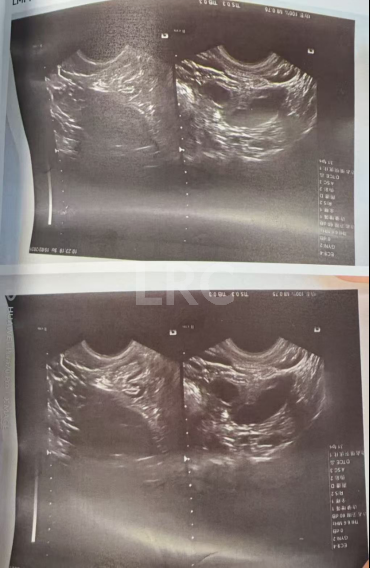

促排第九天

阴超检查:

- 右侧卵泡 9 颗 (20,20,20,20,20,20,19,18,17,16,16,15,13mm)

- 左侧卵泡 8 颗 (20,20,18,18,17,17,16,16,15,14mm)